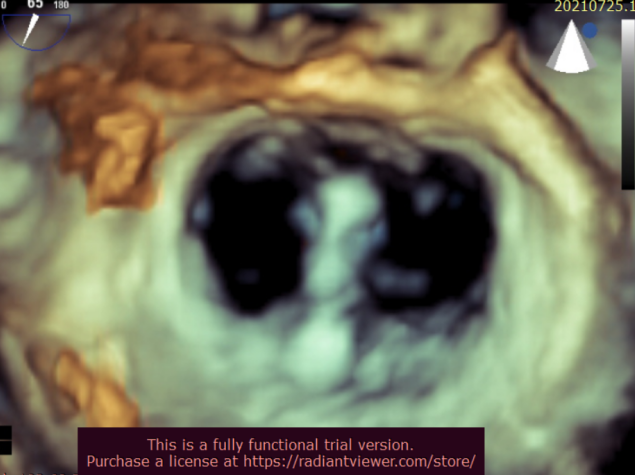

北部战区总医院心内科团队成功完成全新经股静脉缘对缘瓣膜修复系统 全国多中心临床研究首例植入手术